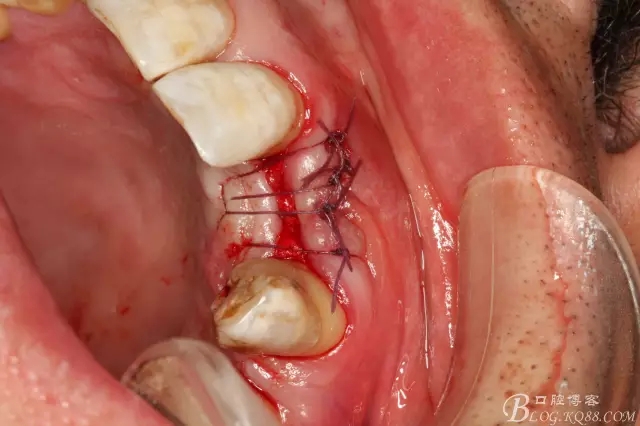

圖6.切開、翻瓣、清理牙槽嵴骨面上的纖維結(jié)締組織。

圖7.植入種植體。奧齒泰:直徑3.5mm。長(zhǎng)度11.5mm。

圖8.植體頰側(cè)有約2mm間隙,植入bicon骨粉。

圖9.表面覆蓋膠原蛋白海綿

圖10.縫合